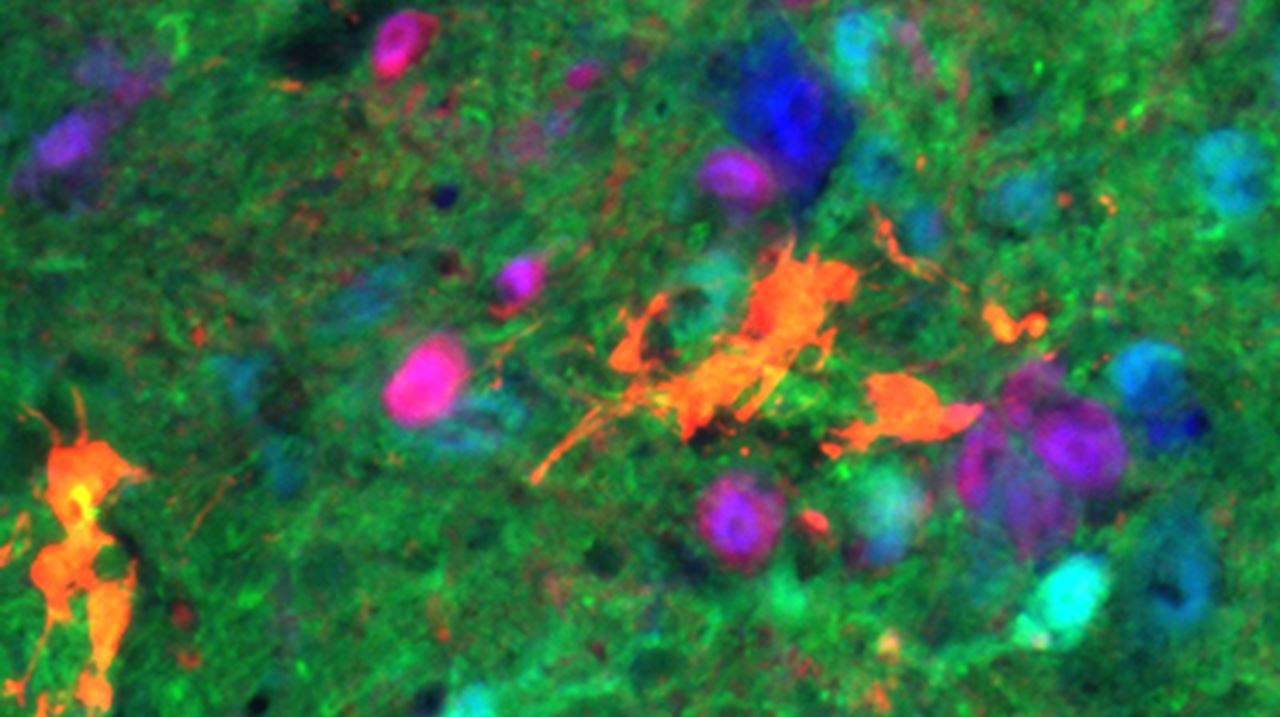

To test their hypothesis, the Drexel team collaborated with Shelly Sakiyama-Elbert, PhD, a cellular engineer at the University of Texas, to differentiate embryonic stem cells into V2a interneurons and combine them with neural progenitor cells from a rodent spinal cord. Once combined, the V2a cells were transplanted into 30 animals with high cervical moderate-severe injuries.

One month following transplantation, the donor cells had survived and become mature neurons in all 30 animals. Recording activity of the diaphragm muscle, the researchers found that breathing significantly improved in the animals that had received V2a interneurons compared to the controls.